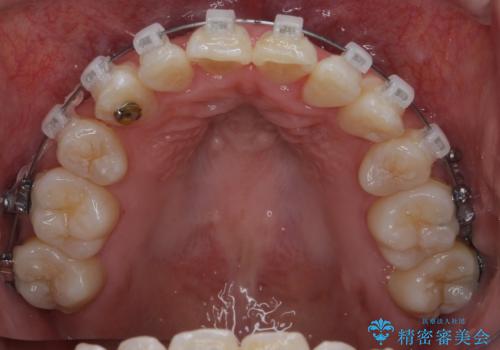

上下左右4本抜歯の可能性を説明していましたが、実際は上顎2本の小臼歯抜歯で済みました。

矯正用インプラントを使用して治療しています。

上下の顎の幅もあっておらず、成人でしたが手術なしで上あごを骨から広げる処置(急速拡大装置)を行いました。